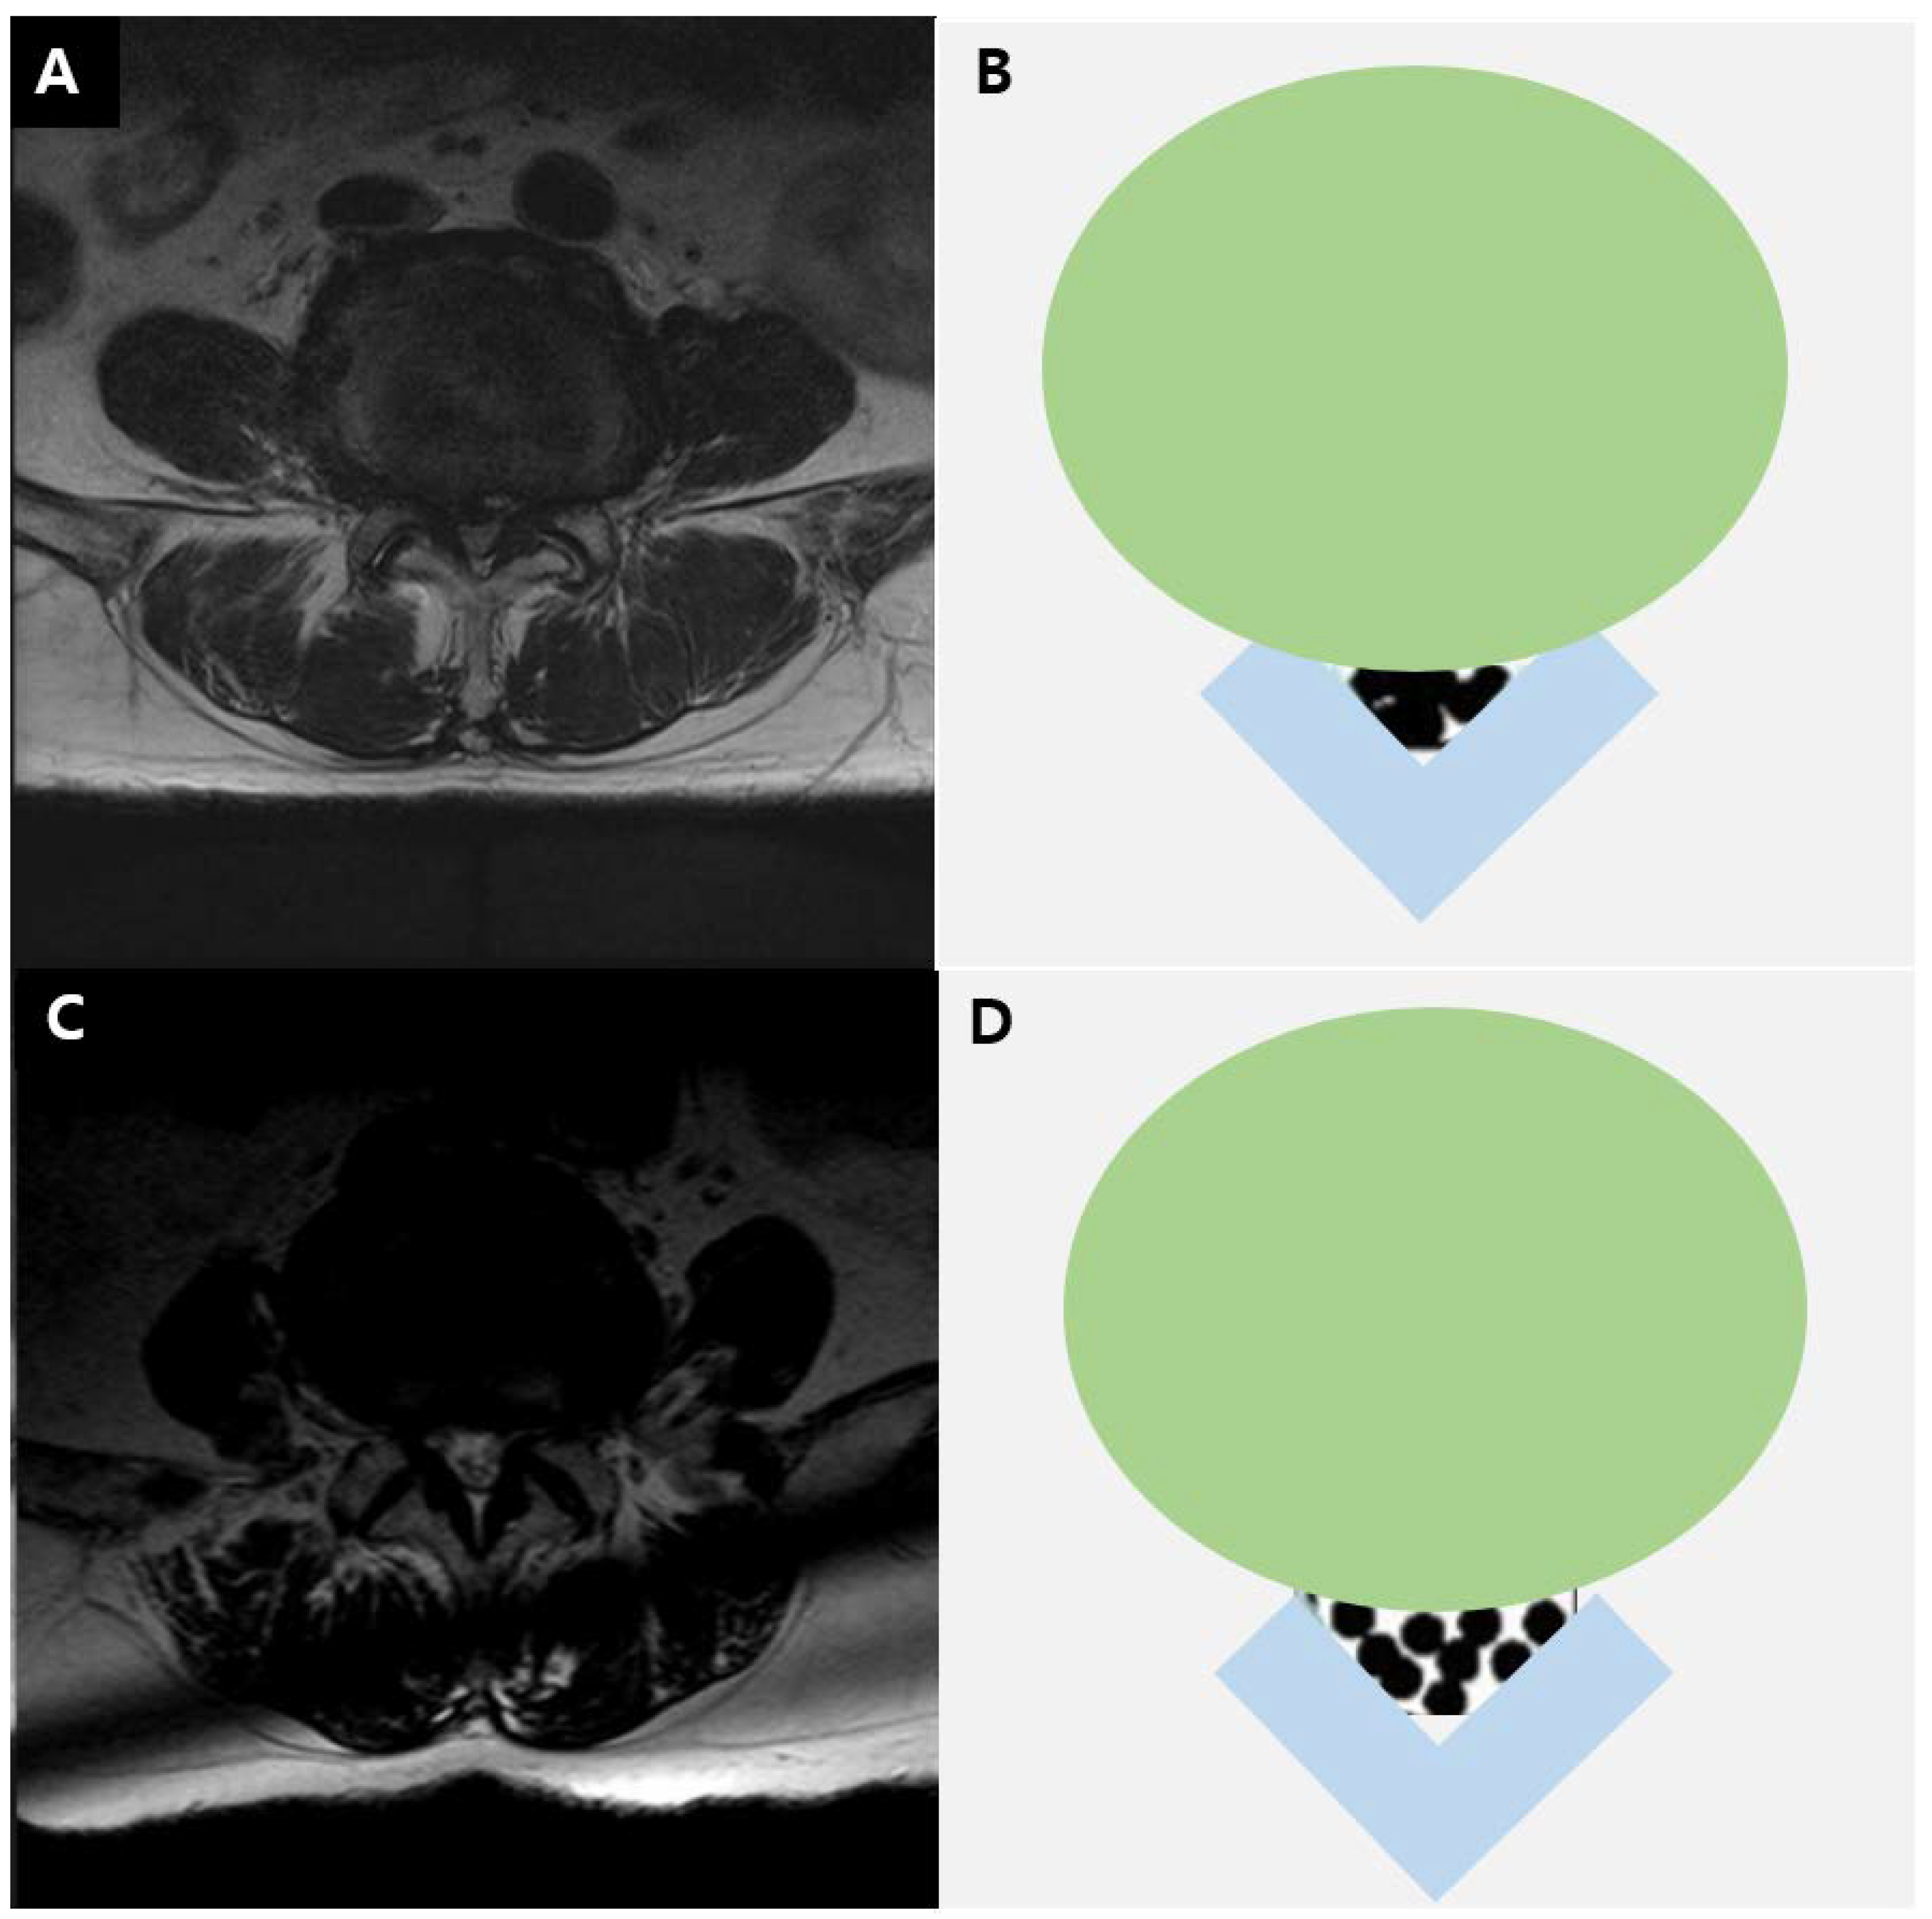

The severity of LCSS was assessed on MRI at the L4–5 level, based on the grading system proposed by Lee et al. (Figure 1) [14]. Grade 0 corresponded to no LCSS; grade 1 to mild stenosis, with clear separation of each cauda equina nerve root; grade 2 to moderate stenosis, with some cauda equina aggregation; and grade 3 to severe stenosis, with the entire cauda equina appearing as a single bundle.

Figure 1.

T2-weighted axial magnetic resonance image in a 73-year-old man (A) and diagram (B) showing severe lumbar stenosis. T2-weighted axial magnetic resonance image in a 70-year-old man (C) and diagram (D) showing moderate lumbar stenosis.